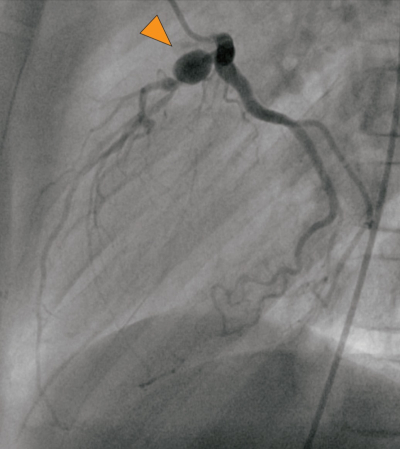

17歳の男子。肝動脈バイパス術後の定期診察で来院した。3歳時に川崎病と診断され入院加療となった。冠動脈瘤が認められたため、退院後、冠動脈病変についてもフォローアップが行われた。8歳時に施行された冠動脈造影では、左右冠動脈に病変が認められた。その際の左冠動脈の造影像を別に示す。その後、左右の冠動脈に1本ずつバイパス血管吻合術が行われた。

b. 左冠動脈の瘤病変(▲)は左回旋枝に存在している。